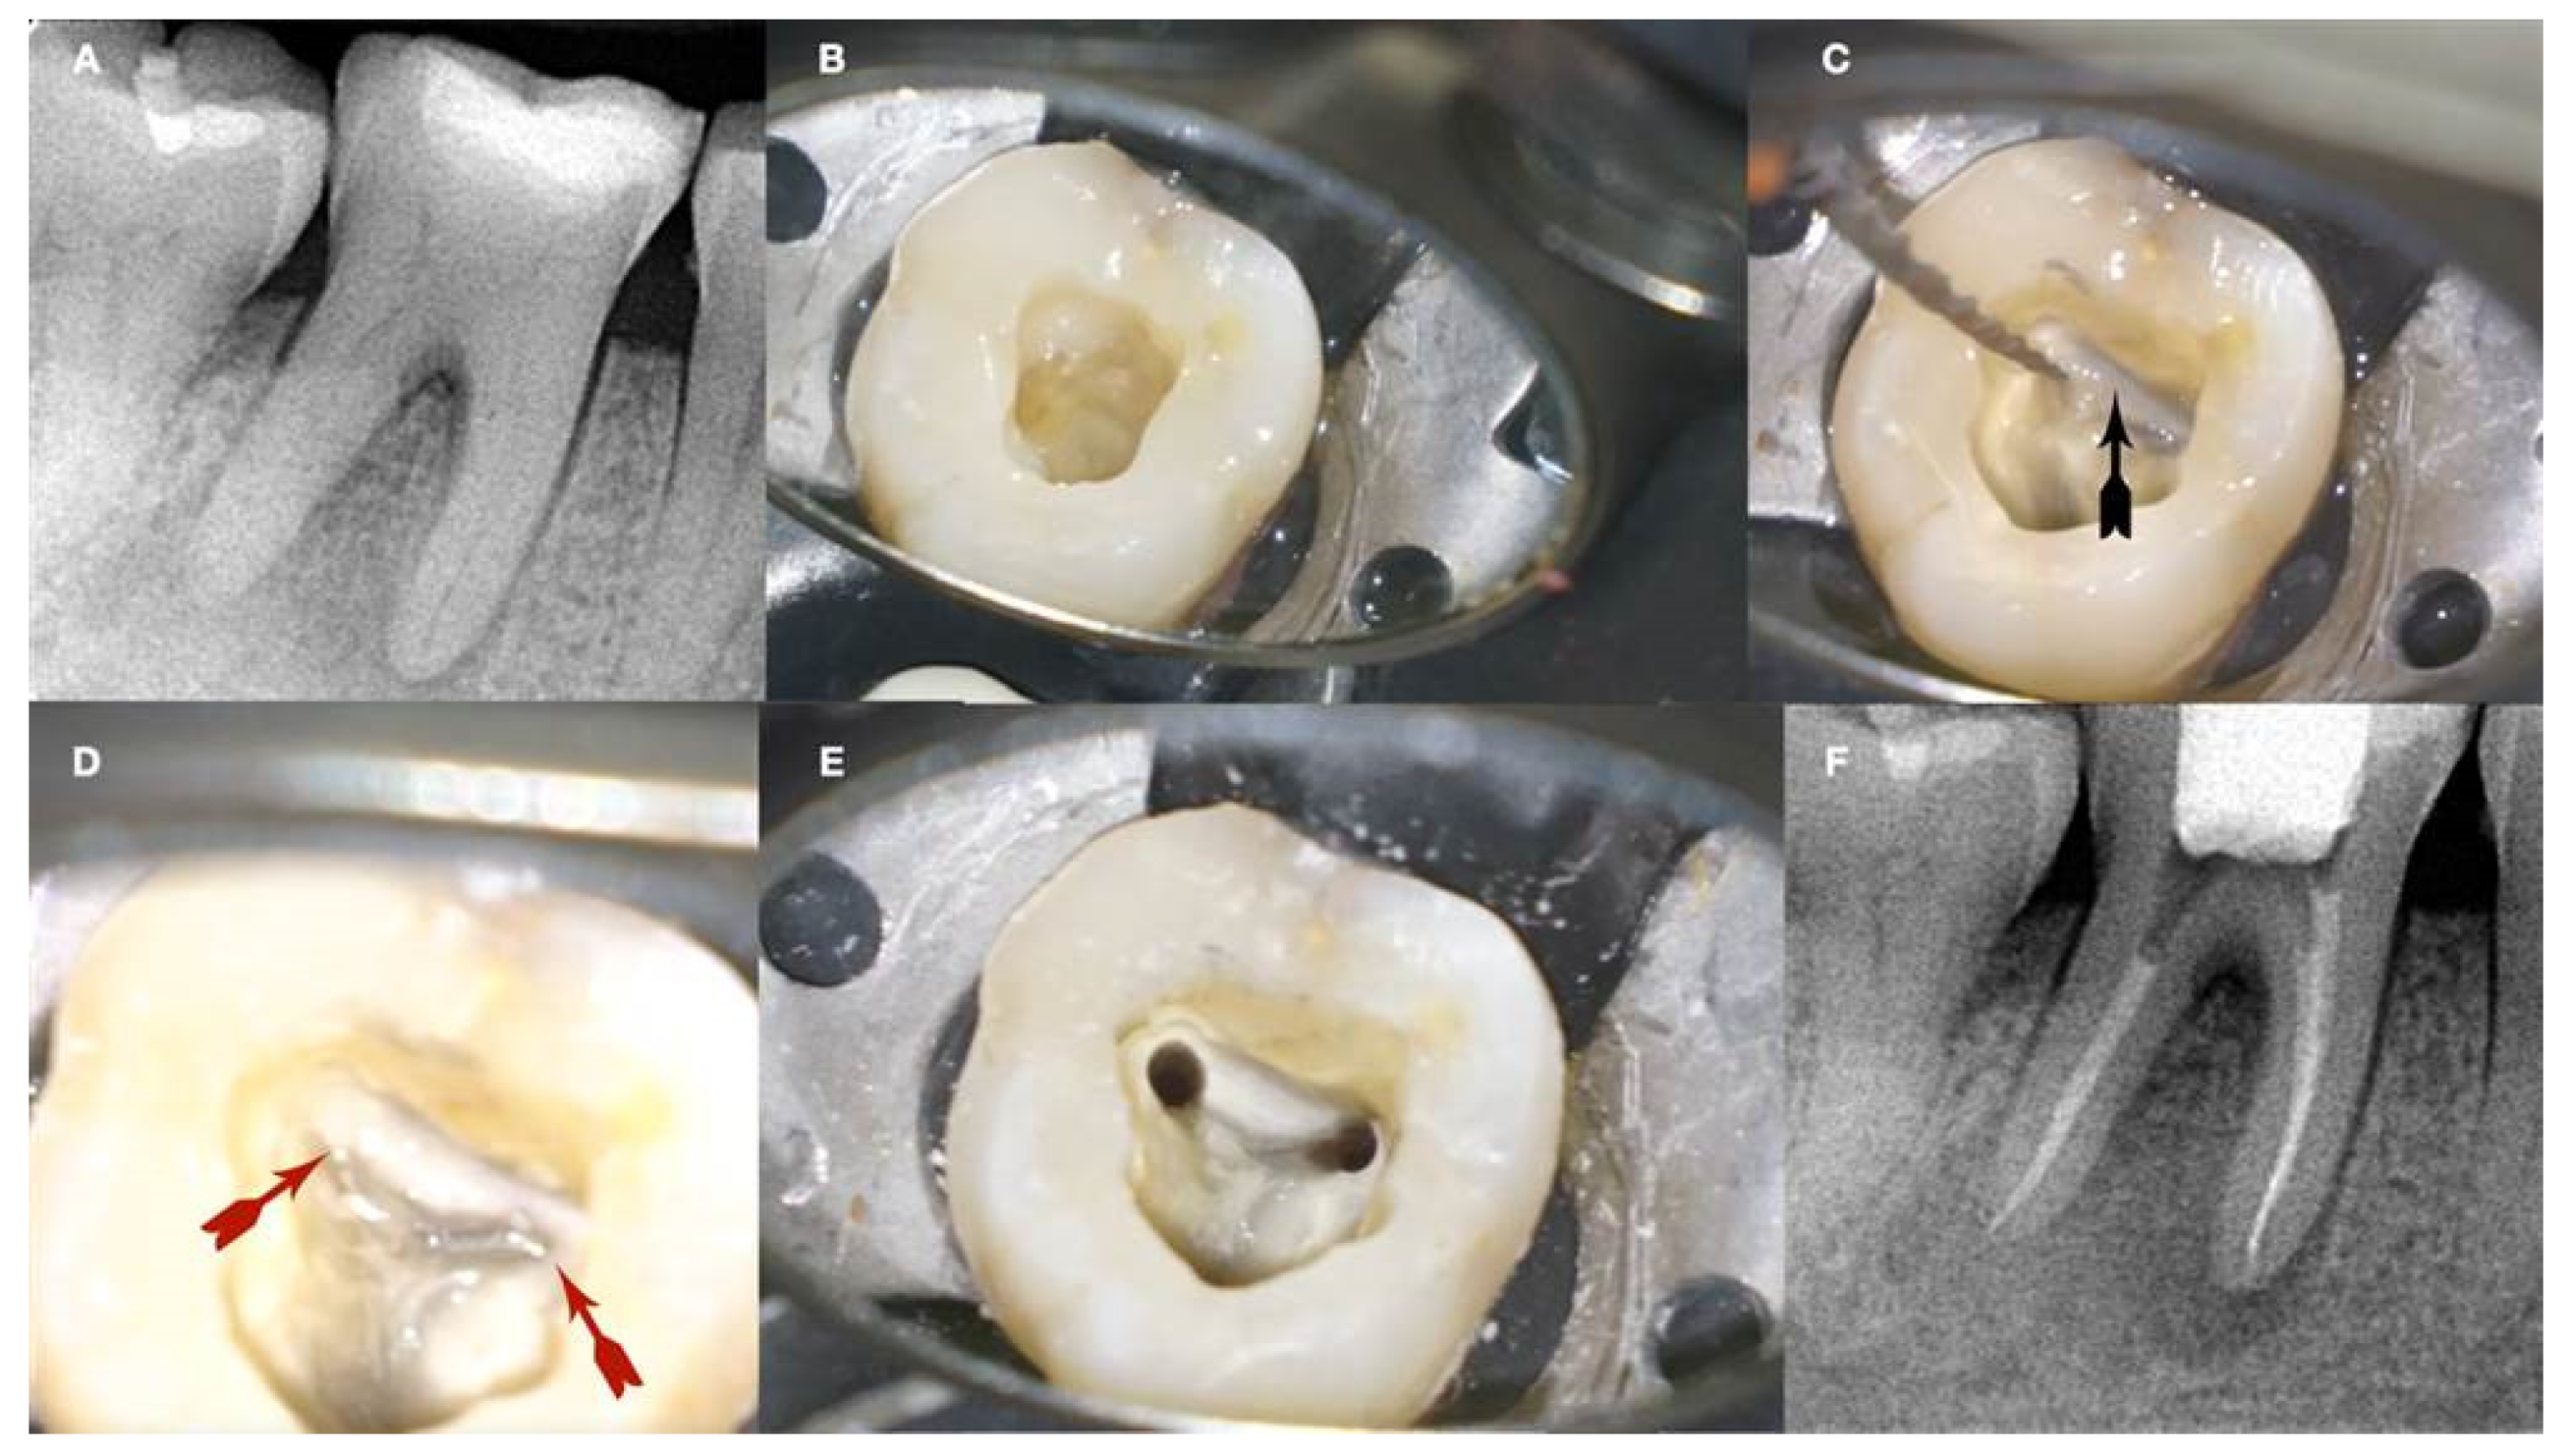

The EDM tip when pressed against the calcification carves its way through, creating an initial dimple in the calcified canal orifice (

Figure 9h,j,i). The carving of the pilot dimple is facilitated with the use of a continuous chelation irrigation technique (

Figure 9e).

Figure 9.

a. Radiographic image of an extracted partially calcified maxillary premolar, b, magnified view at the level of the axial cut (grey area in a), c, & d. creation of initial access dimple in the white spot indicating the calcified orifice, e. continuous chelation of the cut dentinal surface, f & g. initial unsuccessful attempt to negotiate the calcified canal orifices with D- finder files iso 08, h. Fitting of the tip of an EDM file (Hyflex EDM -one file, Coltene) in the dimple without activation, j & i. On-spot buckling activation test (BAT) negotiation of the EDM files, k. negotiation of the 08 d-finders inside the calcified canals after the BAT negotiation technique removed coronal calcified canal obstructions, l. radiographic verification of calcified canal negotiation.

The initial dimple is deepened progressively in a crown-down sequence until a patent pathway is met and confirmed (

Figure 9 and

Figure 10). Total obliteration of the canal space is very rare.

Figure 10.

Buckling Resistance Activation Test (BRAT) negotiation of calcified canals graphic explanation a. Long-shafted bur access cavity preparation, b. continuous chelation concept irrigation and D-finder negotiation test, c. long shafted access bur of smaller diameter insertion without activation (tactile feedback), d. single stroke activation of the bur (Tactile Controlled Activation), e. continuous chelation concept irrigation and D-finder negotiation test. If no negotiation continue to the next step, f. EDM or Active tip file placement inside the access dimple without activation, g. Activation of the EDM file at 500rpm/3NCM and apply vertical axial pressure against the calcified canal entrance (long press-release twice), h. continuous chelation concept irrigation and D-finder negotiation test. If no negotiation continue to the next step, i. EDM or Active tip file placement deeper inside the dedicated access dimple without activation, j. activation of the EDM file at 500rpm/3NCM and apply vertical axial pressure against the calcified canal entrance (long press-release twice). As the file goes deeper inside the root the buckling resistance of the file is increased because the lateral walls won’t allow the file to buckle and succumb. The axial pressure is transported to the file tip allowing the file to penetrate, k. continuous chelation concept irrigation and D-finder negotiation test. If no negotiation continues to the next step, l. EDM or Active tip file placement deeper inside the dedicated access dimple without activation, m. activation of the EDM file at 500rpm/3NCM and apply vertical axial pressure against the calcified canal entrance (long press-release twice), n. continuous chelation concept irrigation and D-finder negotiation test, o & p. If no negotiation repeats the previous steps.